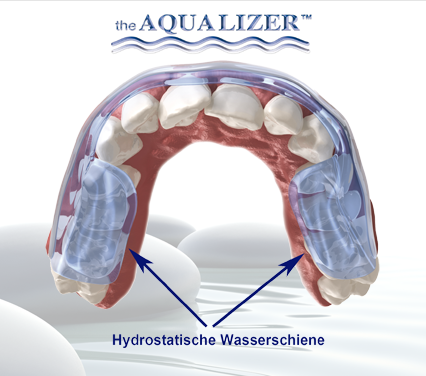

AQUALIZER™ - (аква+еквілібрація) - це наповнена водою накусочна шина, яка функціонує за гідростатичним принципом

Функціонування аквалайзера

Замкнена рідинна система аквалайзера діє динамічно та постійно, щоб збалансувати обидві сторони щелепи. Нижня щелепа завжди встановлюється в оптимальну позицію. Аквалайзер функціонує за гідростатичним принципом, який вперше було описано фізиком Паскалем. Згідно цього принципу, в замкненій рідинній системі тиск розподіляється рівномірно в усіх напрямках. Аквалайзер ідеально використовує цей принцип як саморегулююча шина. При цьому всі оклюзійні сили спрямовуються симетрично відносно осі, таким чином виникає стабільна оклюзія. Зуби просто можуть ковзати по гнучкій та гладкій поверхні прикусної подушечки аквалайзера. Гнучкі подушечки між обома оклюзійними поверхнями аквалайзера виключають усі контакти “зуб-до-зуба”. Функції пропріорецепторів зубів, м`язів та щелепних суглобів нейтралізуються. Звичайна, керована пропріорецепторами оклюзія усувається. Нижня щелепа, з допомогою розслаблених м`язів, може рухатися в комфортну позицію. Вже за декілька хвилин нова, розслаблена позиція усуває примусову болючу звичайну оклюзію пацієнта. В пацієнтів з хронічними болями цей процес триває трошки довше.